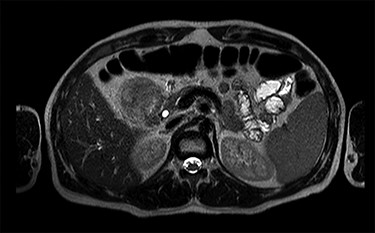

Blood tests showed no anaemia nor leukocytosis but transaminases and C-reactive protein were slightly elevated. He had an abdominal and thoracic computerized tomography scan (CT) done in the ED that revealed a large duodenal tumour, approximately 6 cm diameter, with an associated intramural haematoma and one enlarged lymph node in the liver pedicle, 19 × 13 mm (Figs 1 and 2). There was no distant metastasis. Additionally, he underwent an upper digestive endoscopy in the ED, confirming the presence of an extensive, nodular, polypoid and obstructive duodenal tumour in its first and second portions, including the major papilla. However, biopsies turned out to be inconclusive. Later, he also had a magnetic resonance done that ruled out invasion of adjacent structures, except for the pancreatic head. Finally, he underwent an endoscopic ultrasound (EUS) with biopsies showing a duodenal NET, with diffuse expression of CK7, chromogranin and synaptophysin, and Ki-67 expressed in less than 2% of the cells.

MRI scan—axial view of the large duodenal mass. Note the solid mass, enhanced by paramagnetic contrast, in the medial wall of the duodenum, invading the pancreatic head parenchyma. More proximally, in the first portion of the duodenum, there is a heterogeneous mass, non-enhanced by contrast, suggestive of an intraparietal haematoma.